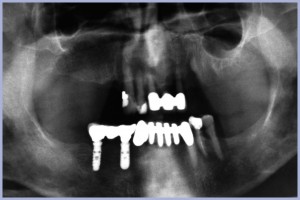

Dopo un attento esame sia clinico che radiologico (Figg. 1, 2) e una TC iniziale si decide per la realizzazione di una protesi “All-on-four”, una protesi fissa avvitata su 4 impianti a carico immediato. Data la necessità di inclinare i due impianti distali per ridurre il più possibile i cantilever protesici e l’intenzione di sfruttare due siti post-estrattivi per l’inserimento degli impianti centrali, si decide di posizionare 3 impianti Max Stability 3,75 x 14 mm e un impianto Max Stability 4,5 x 14 mm.

L’ortopantomografia di controllo immediata conferma il corretto posizionamento degli impianti, dei monconi e della protesi (Fig. 11).

- Fig. 1 – Ortopantomografia iniziale

- Fig. 11 – Ortopantomografia post intervento